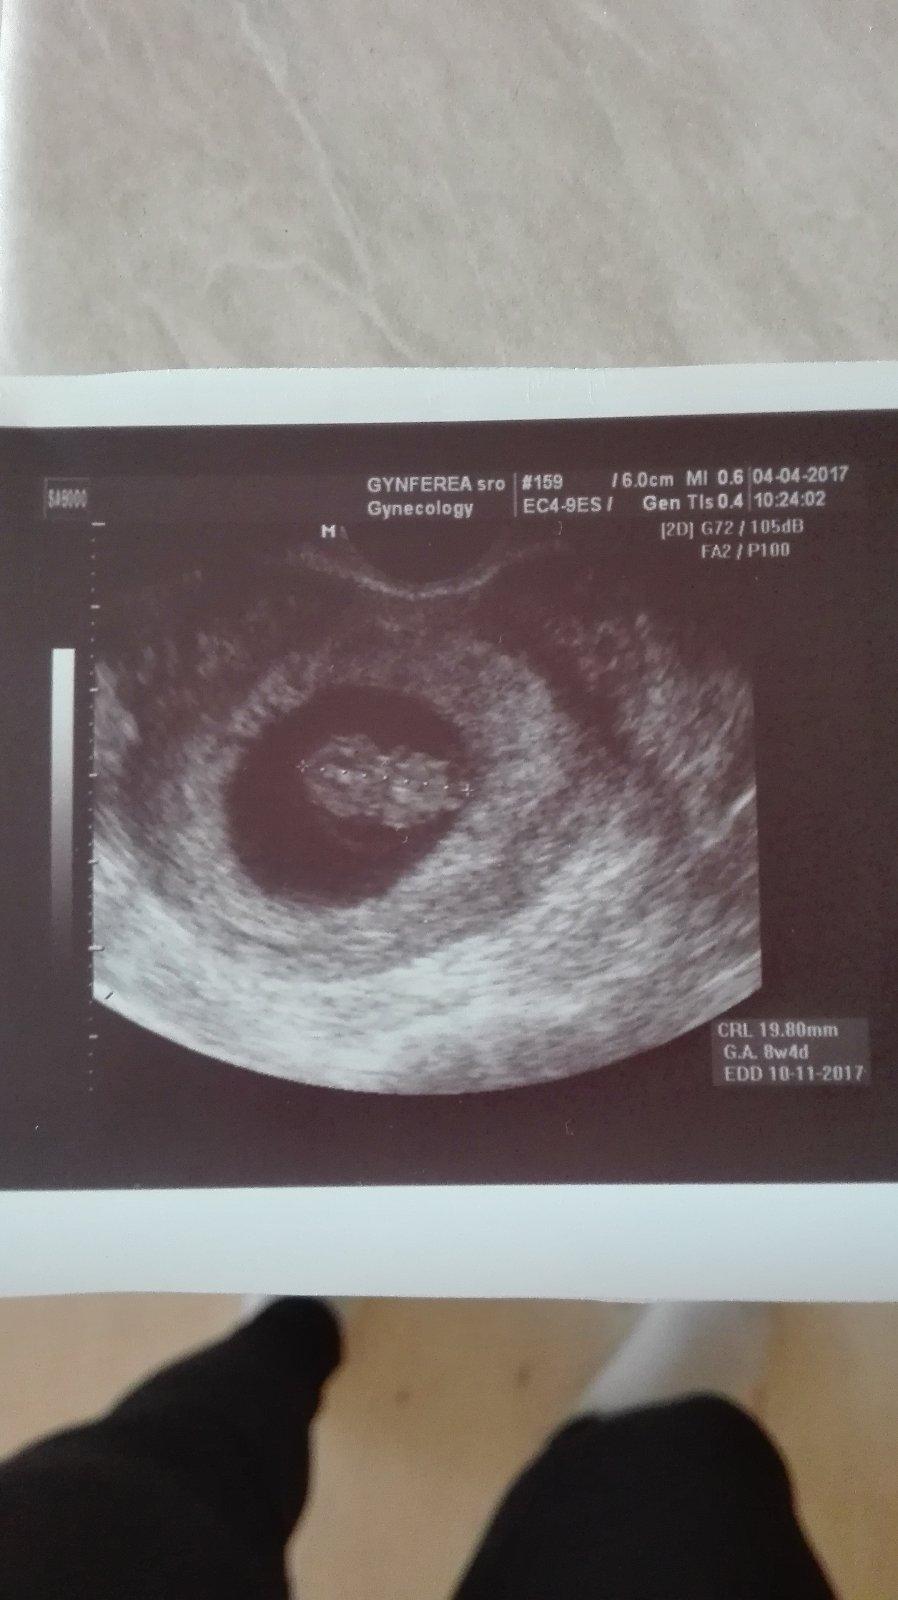

@nmnicka no nie som lekar, ale ak by to mali byt dvojicky, tak asi jednovajecne. Dvojvajky vyzeraju takto